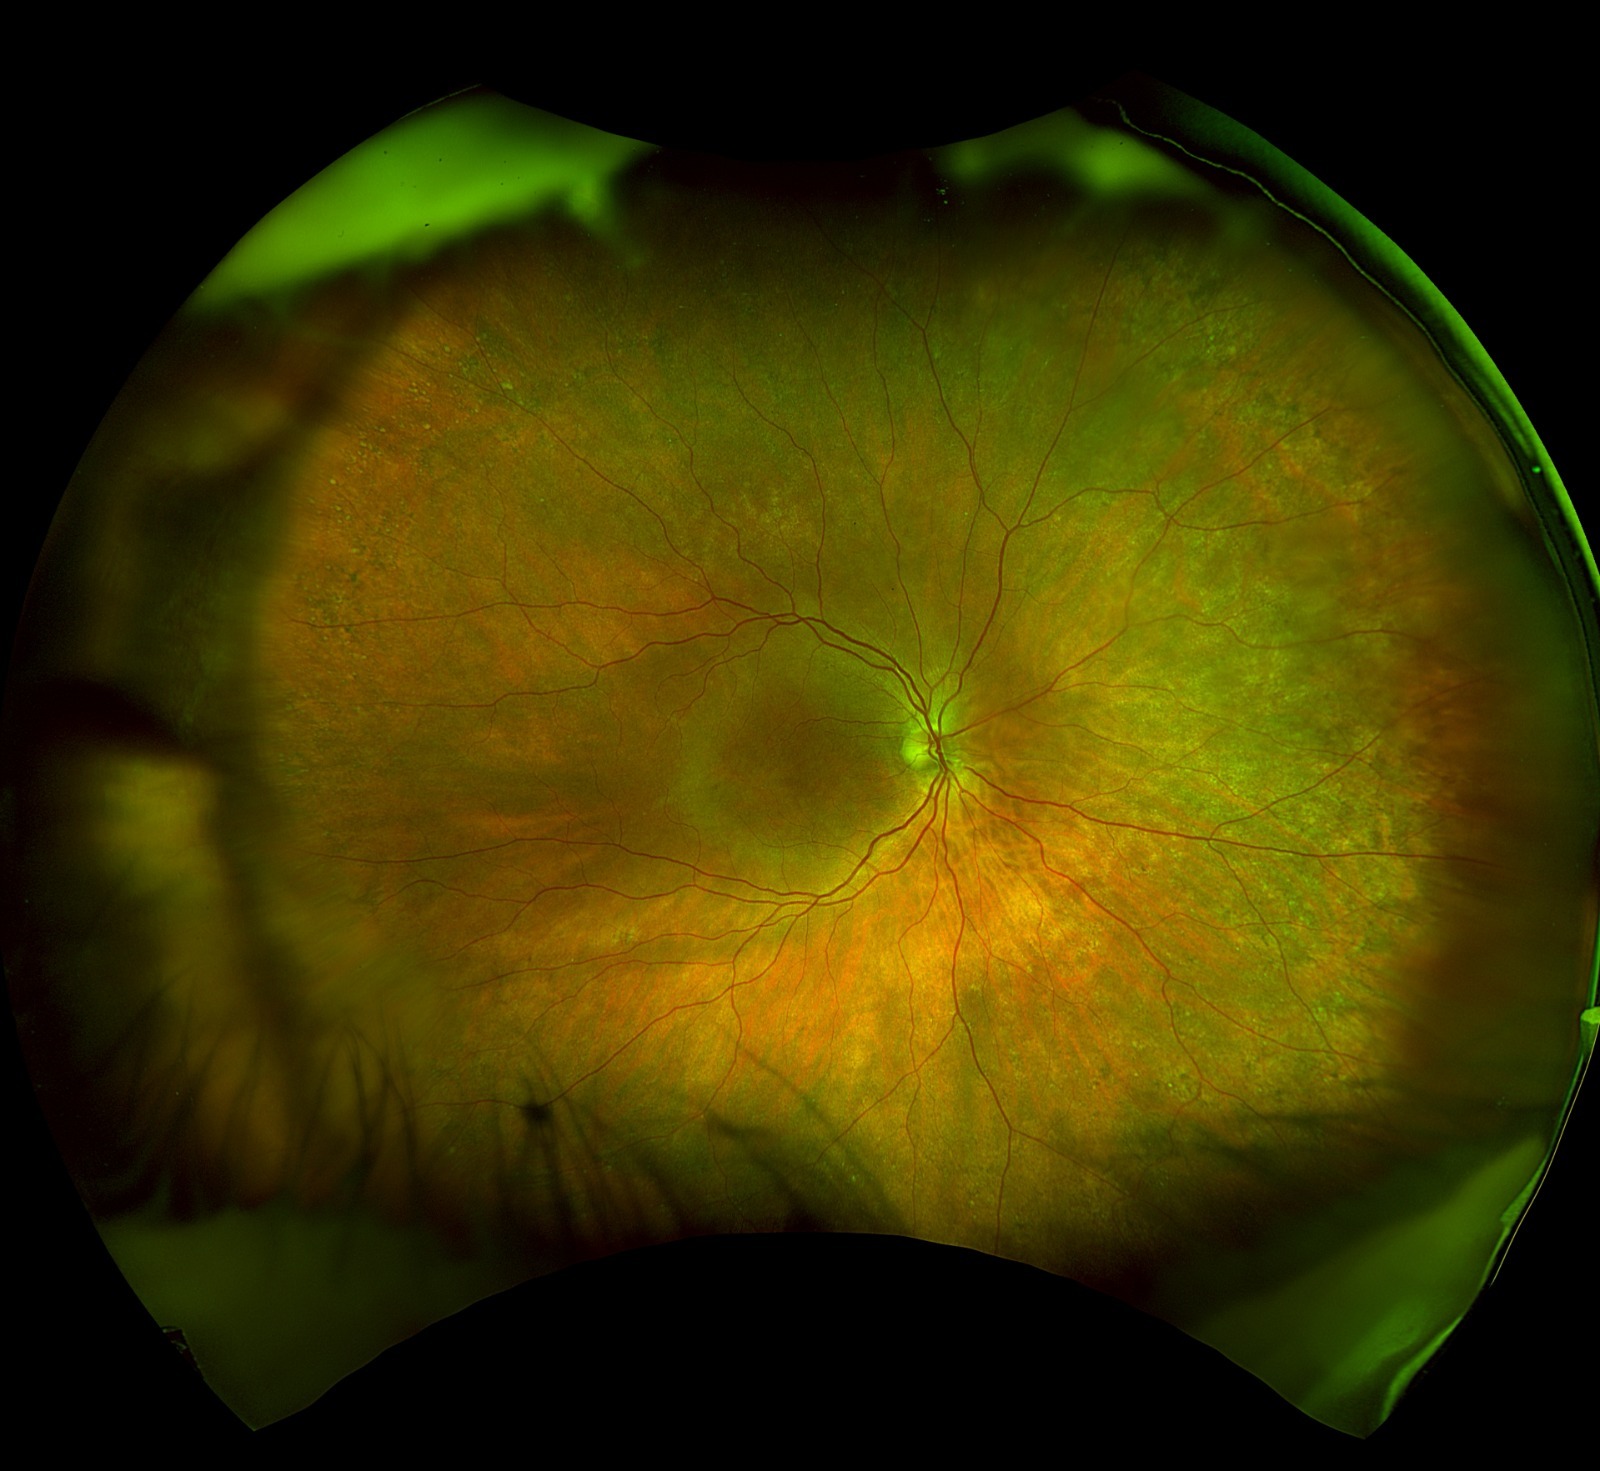

Reunión SOCHIREV

Una sesión que contó con la participación de destacados especialistas.